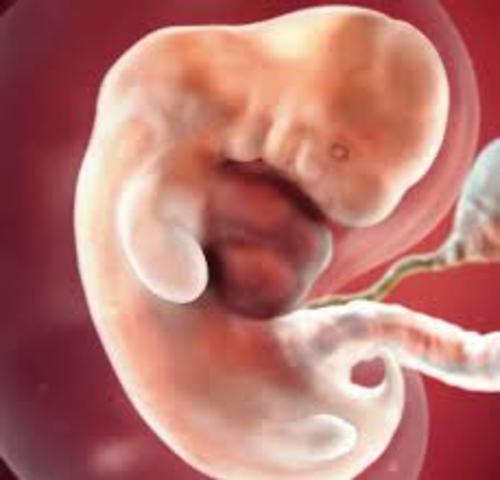

• semana 2 de embarazo

semana 2 de embarazo

El embarazo se mide en semanas a partir de la última regla, pero el bebé se concibe antes. A partir de la semana 2 del embarazo, se desarrolla lo que llamamos embrión, que tiene básicamente una cabeza, un tronco y una cola rizada. Las primeras semanas de embarazo son muy importantes porque, aunque todavía es un embrión, empieza a desarrollar los cimientos de lo que serán sus órganos, sus rasgos y su sistema nervioso.